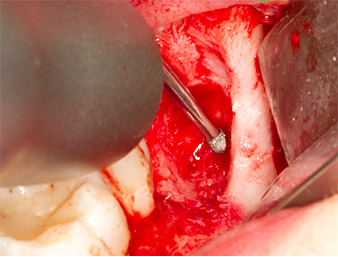

Using an instrument for periodontal debridement (Piezomed P1), the periodontal ligament space of the radix relicta was then widened minimally (Fig. 8).

The same activated instrument was inserted into the root canal and loosened the fragment as a result of its micro-oscillating vibrations (Fig. 9, 10).

Piezomed P1

Fig. 9: The Piezomed P1 instrument is recommended by the manufacturer primarily for periodontal debridement but is also suitable for surgical purposes. Here it is placed in the root canal after minimal widening of the periodontal ligament space.

Fig. 10: Due to its slender shape, the instrument can penetrate the root canal and remove the root remnant by means of micro-oscillation (vibration).

It was then possible to remove the approximately six-millimetre-long root remnant in one piece with the P1 attachment (Fig. 11).